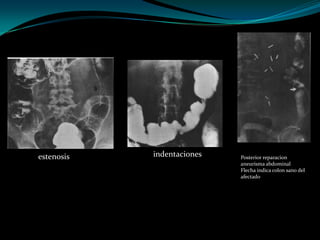

Multiples indentaciones   Ulceras superficiales   Impresiones digitiformes

estenosis   indentaciones   Posterior reparacion

aneurisma abdominal

Flecha indica colon sano del

afectado